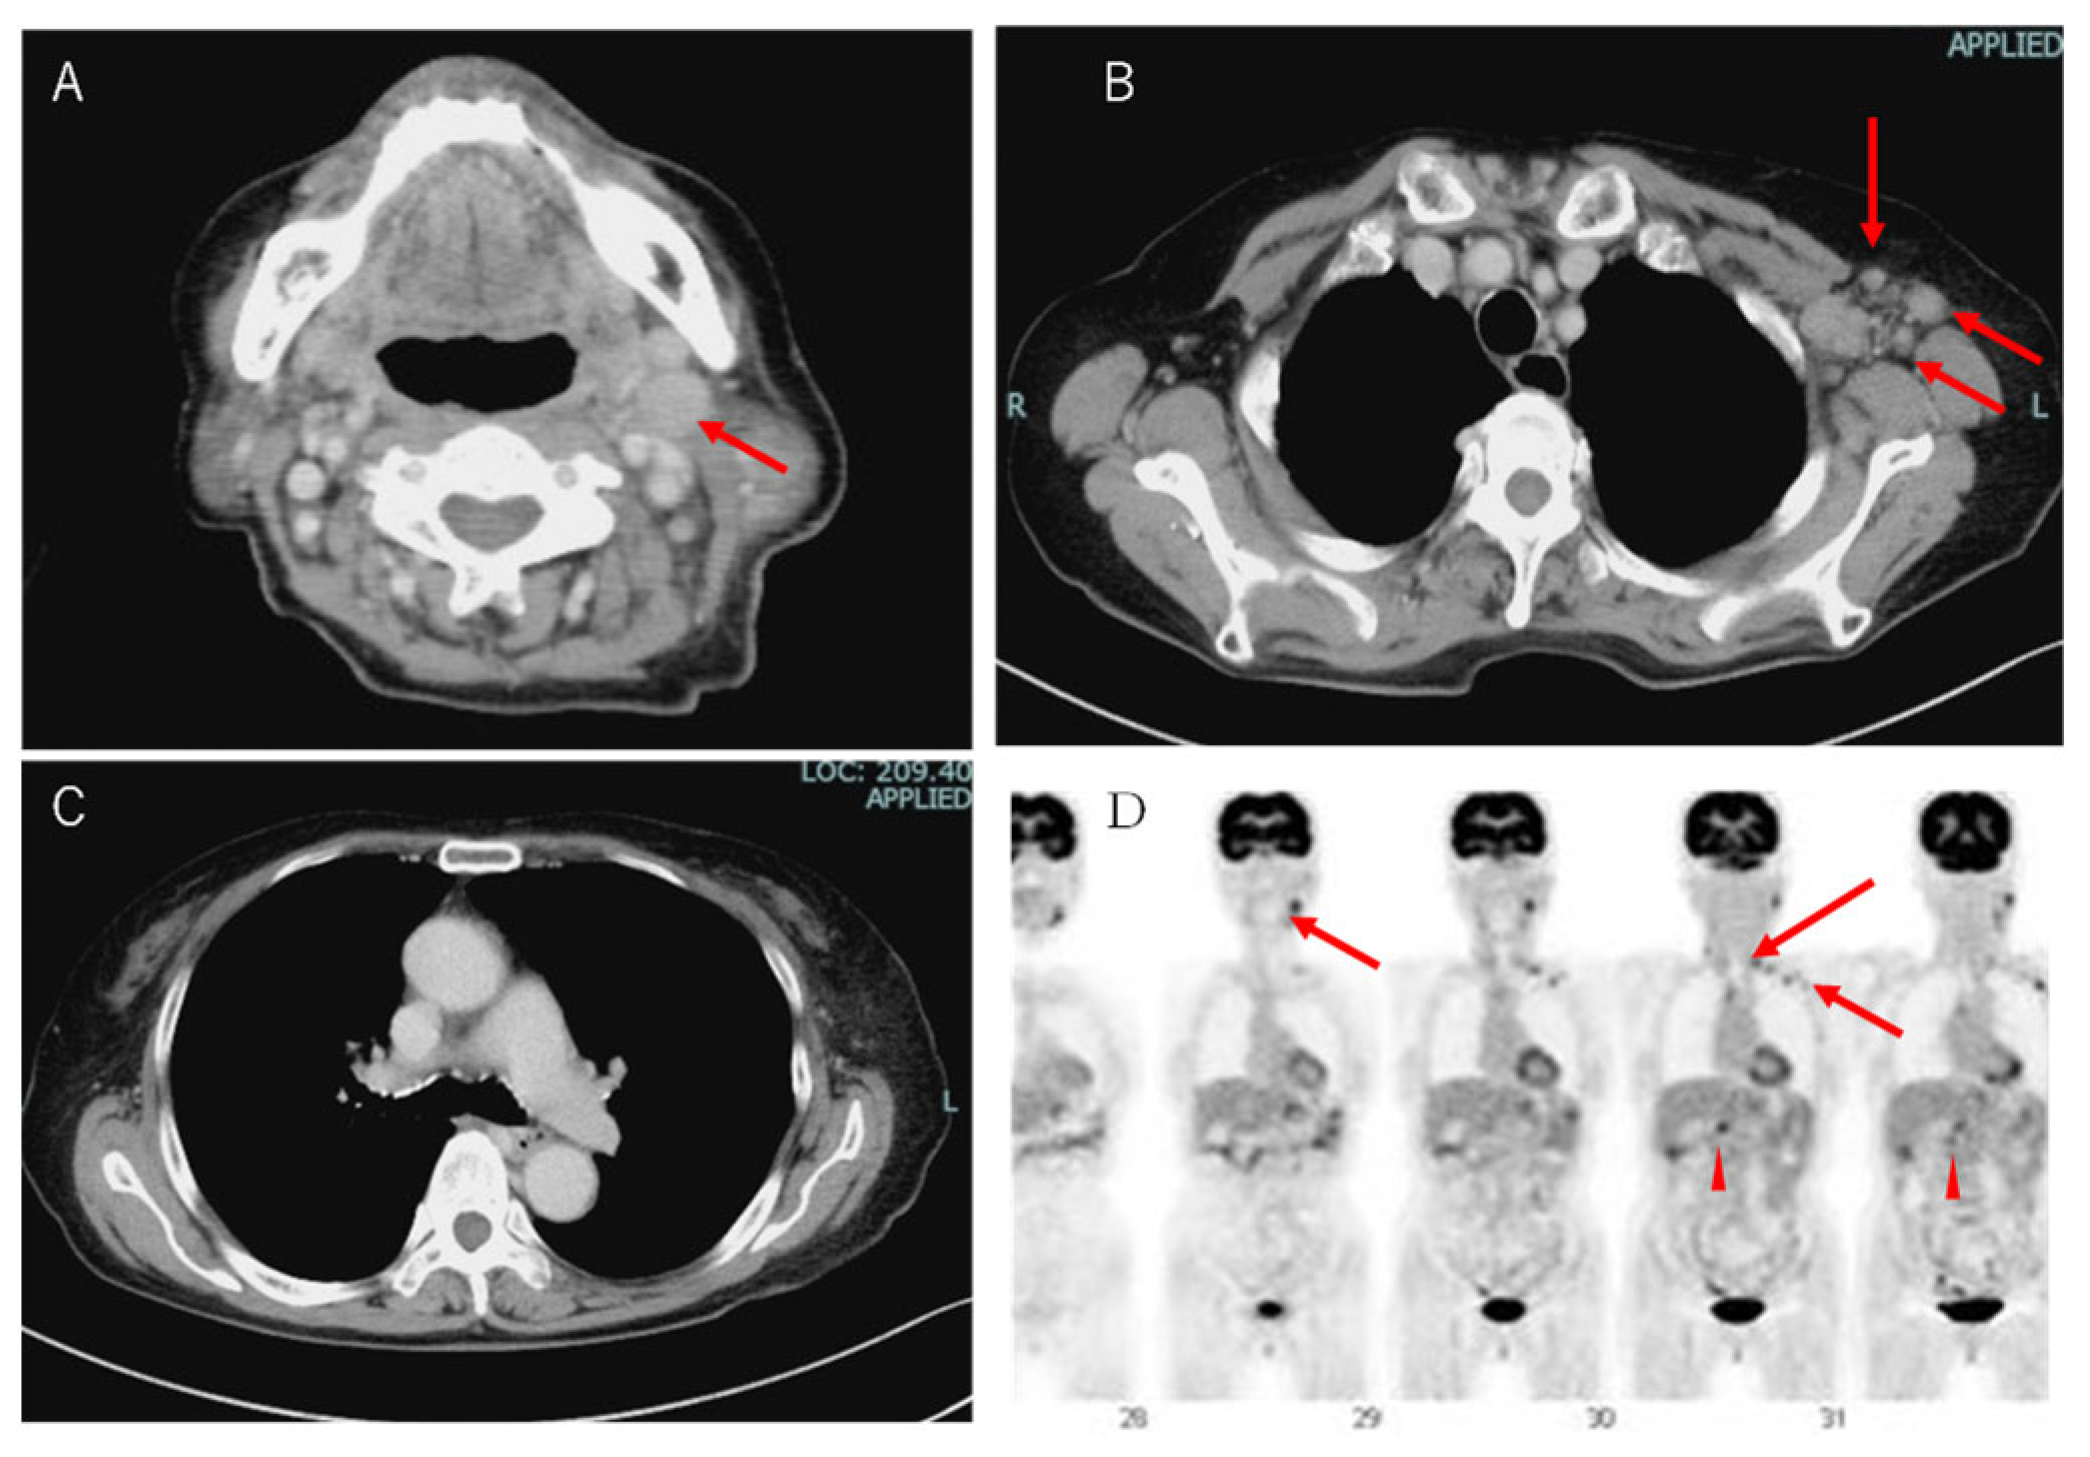

2. Case Presentation Section